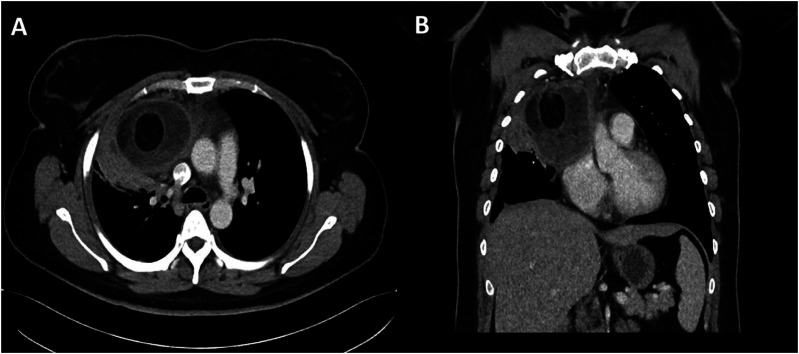

Teratomas are a common type of germ cell tumours which may be benign or malignant. Benign mature teratomas are the most frequent subtype and typically show intralesional fat and calcifications within a cystic mass. Immature/malignant teratomas are usually larger with irregular solid components, coarse calcifications, small amounts of fat, and with or without necrosis or haemorrhage. Teratomas can manifest in various anatomical locations, particularly in the sacrococcygeal, gonadal, mediastinal, retroperitoneal, and intracranial regions. This article explores the imaging characteristics and diverse locations of teratomas as well as discusses about possible differential diagnoses to facilitate early detection and ensure prompt treatment.

Abstract Image